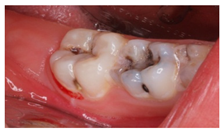

| 2 | An 11-year-old patient.Upon clinical examination, multiple carious lesions are observed in various deciduous teeth and permanent first molars. In tooth 4.6, the patient reported sensitivity to cold stimuli, without episodes of intense pain nor inflammation. Additionally, there is an absence of pain to percussion and physiological probing depth. | ![]() | The diagnosis was reversible pulpitis in an immature tooth. Which treatment alternative would you select for this case? Order the answers from more to less adequate for the treatment of this case. |

| [10,13,14,30,32] | |